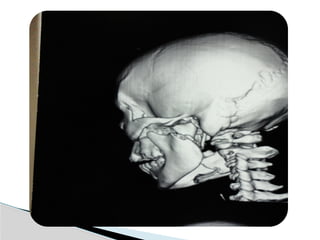

Conventional Radiology

At least 2 views at right angle to each other.

Mandibular series: PA, Lateral oblique or

panoramic, & Towne’s view (projects condyle

below mastoid process).

CT

Significant displacement or dislocation,

mechanical obstruction, mult trauma pt, &

intracapsular fracture.

MRI

St injuries: effusion, visualization of disc.

Imaging

Conventional Radiology At least2 views at right angle to each other. Mandibular series: PA, Lateral oblique or panoramic, & Towne’s view (projects condyle below mastoid process). CT Significant displacement or dislocation, mechanical obstruction, mult trauma pt, & intracapsular fracture. MRI St injuries: effusion, visualization of disc. Imaging